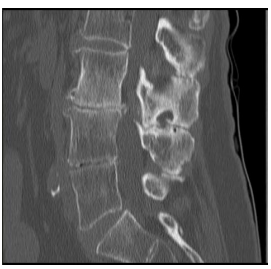

O corte tomográfico sagital da

coluna lombar abaixo ilustra

claramente alterações que possibilitam alguns diagnósticos,

dentre os quais podemos citar: